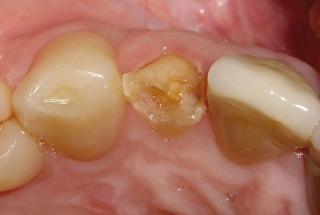

Clinical cases

MPI closely monitors clinical cases in the market to ensure their correct functioning and successful outcome.